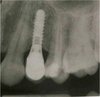

Вообще по идеи лучше всего конечно же ставить импланты ипортные!Ну и какие из этих надежнее или эстетичнее???![]()

Они намного надёжнее и эстетичнеее смотрятся, по сравнению с российскими имплантами!